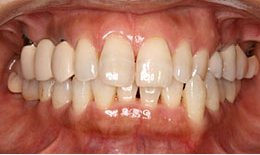

インプラント症例(6) 52歳 女性

治療前

治療後